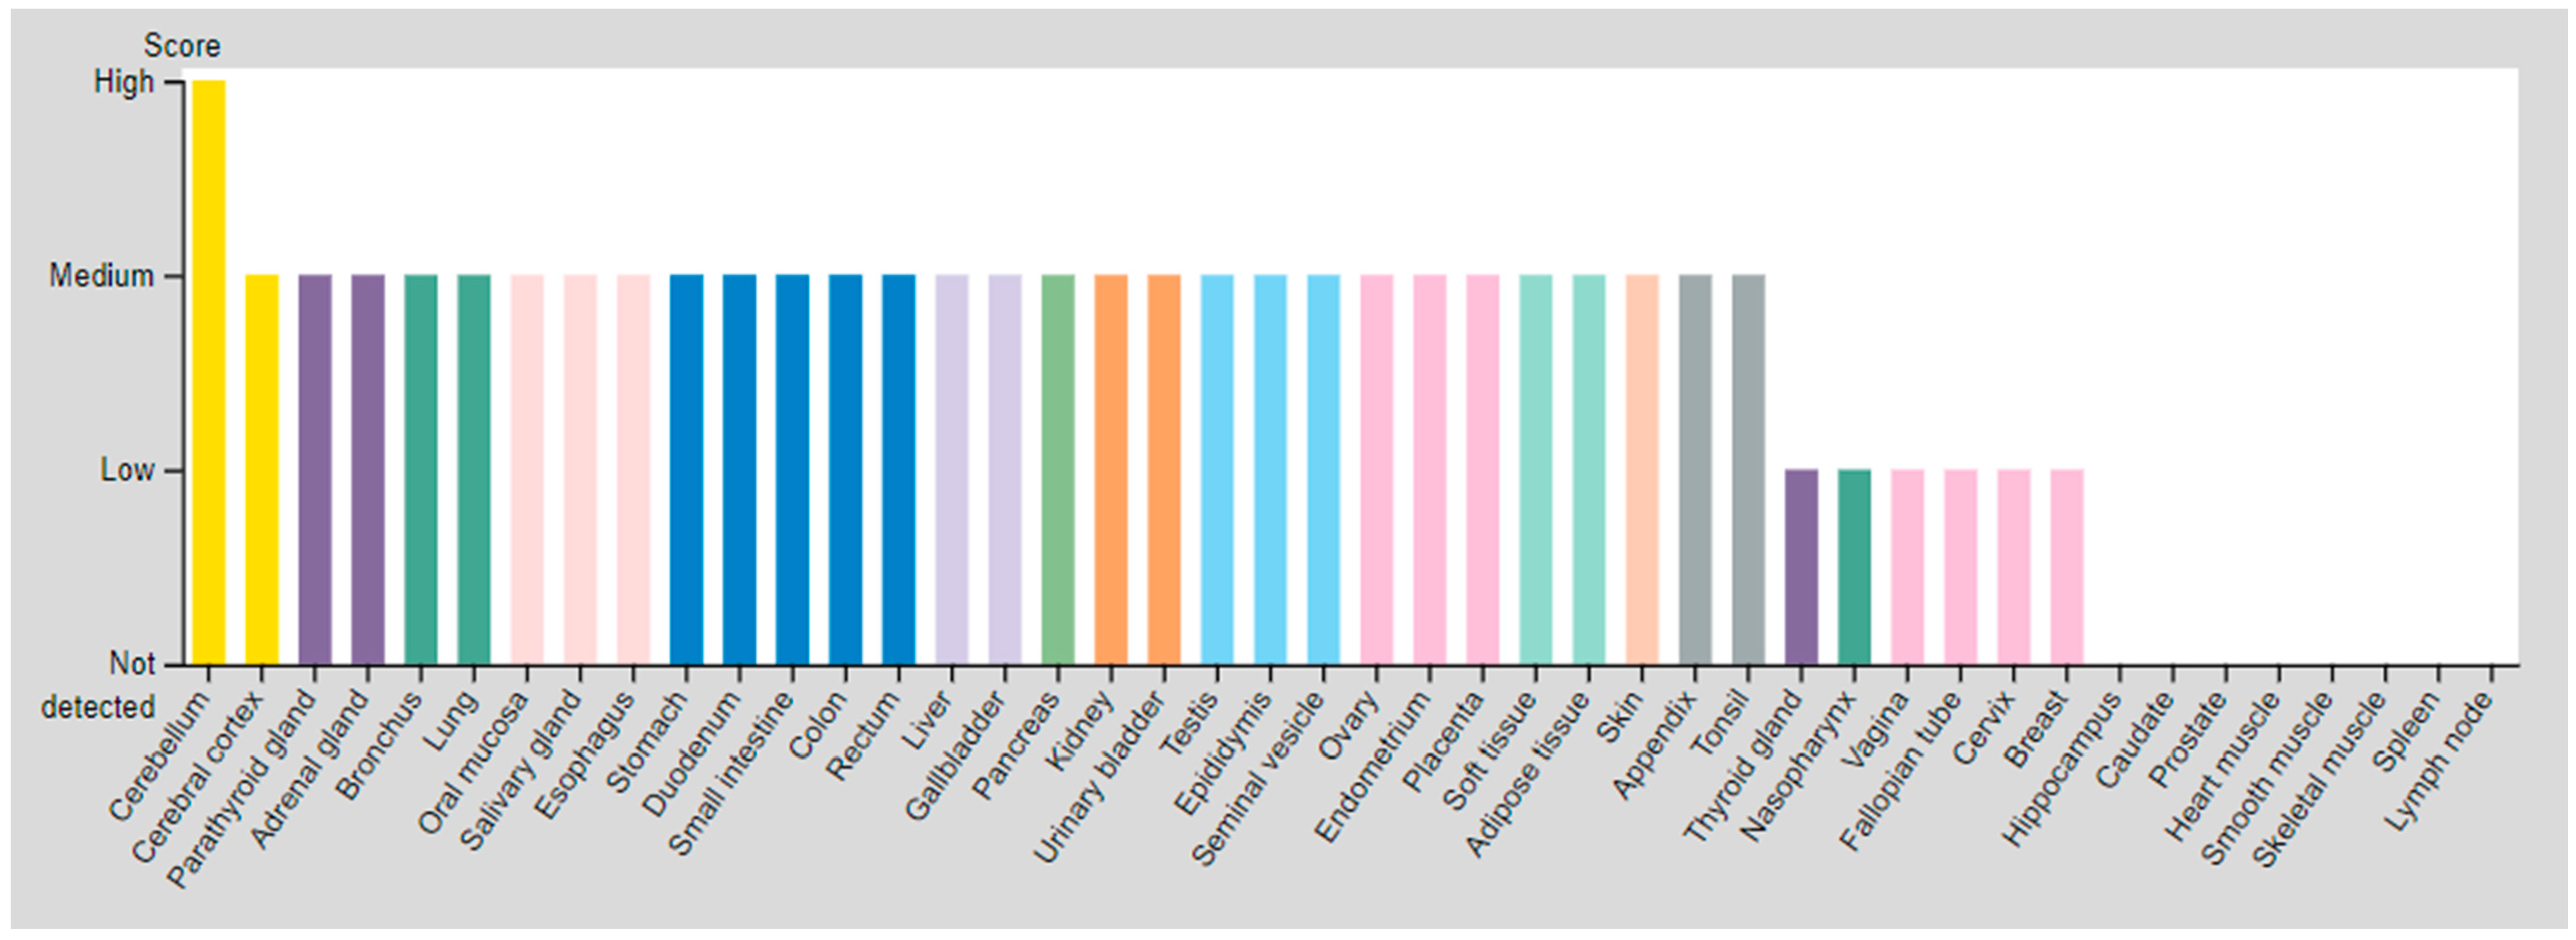

| SSTR | Critical Organs’ Tissue (High Expressed) | Critical Organs’ Tissue (Medium Expressed) | Critical Organs’ Tissue (Low Expressed) | |

|---|---|---|---|---|

| SSTR2 | Cerebellum | Parathyroid gland Adrenal gland Bronchus Lung Oral mucosa Salivary gland Esophagus Stomach Duodenum Small intestine Colon Rectum Liver Gallbladder Pancreas Kidney Urinary bladder Testis | Epididymis Seminal vesicle Prostate Ovary Endometrium Placenta Adipose tissue Peripheral nerve Fibroblasts Keratinocytes Langerhans Melanocytes Epidermal cells Glandular cells Squamous epidermal cells | Cerebral cortex Thyroid gland Nasopharynx Vagina Fallopian tube Cervix, uterine Breast |